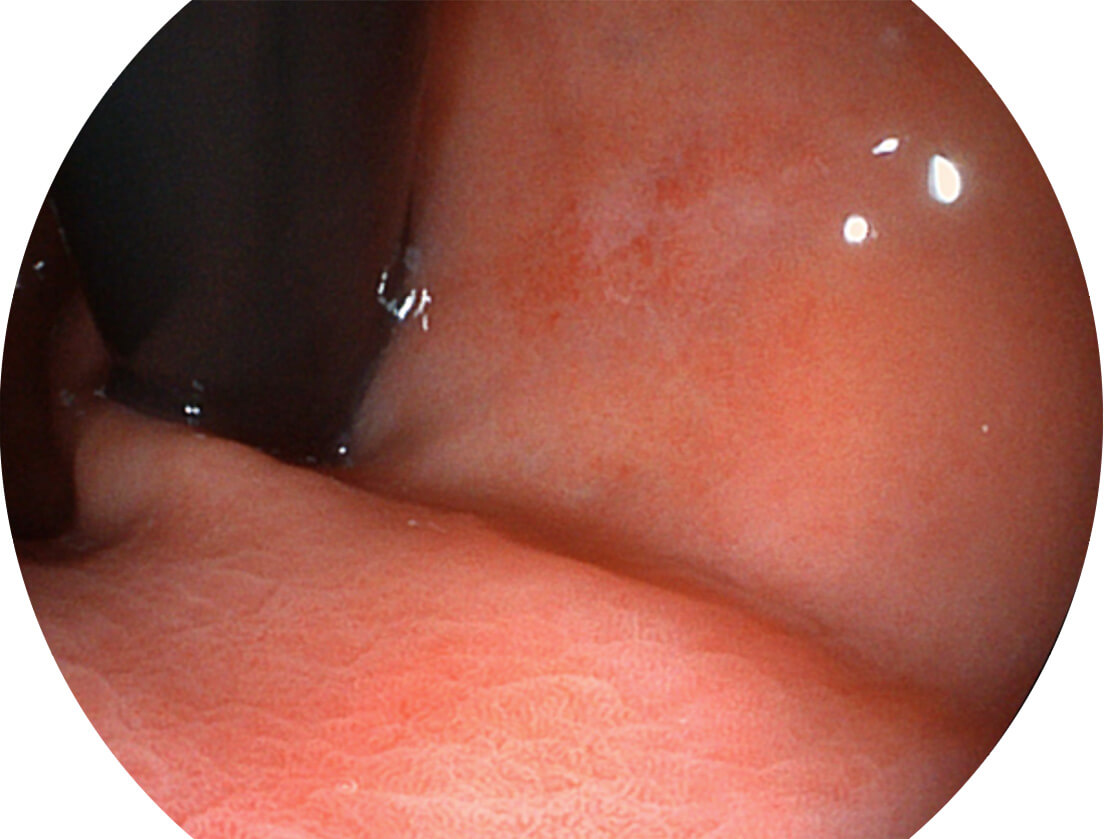

白光图像

白光图像

VIST图像

VIST图像

白光图像

白光图像

VIST图像

VIST图像

白光图像

白光图像

VIST图像

VIST图像

Versatile Intelligent Staining Technology, VIST

强调浅层黏膜结构的同时,保证照明亮度和提升浅层微血管与中层血管颜色对比度,病变边界更清晰。